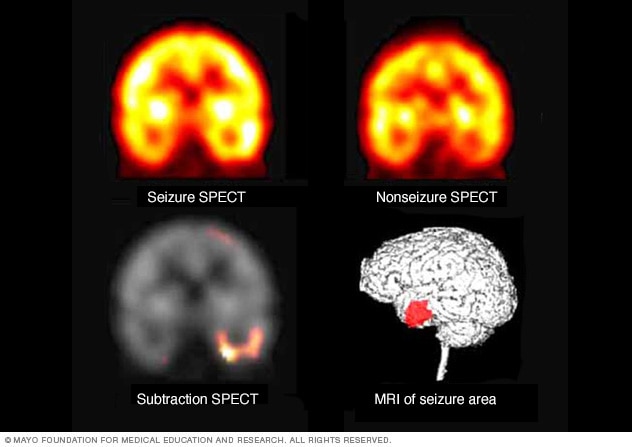

Pinpointing seizure location

These SPECT images show the blood flow in the brain when there's no seizure activity (left) and during a seizure (middle). The subtraction SPECT coregistered to MRI (right) helps pinpoint the area of seizure activity by overlapping the SPECT results with brain MRI results.

-

Single-photon emission computerized tomography (SPECT). This type of test is used if MRI and EEG didn't pinpoint the location in the brain where the seizures start.

A SPECT test uses a small amount of low-dose radioactive material. The material is injected into a vein to create a detailed, 3D map of blood flow during seizures. Areas of higher than typical blood flow may indicate areas where seizures occur.

Another type of SPECT test called subtraction ictal SPECT coregistered to MRI (SISCOM) may provide even more-detailed results. The test overlaps the SPECT results with brain MRI results.